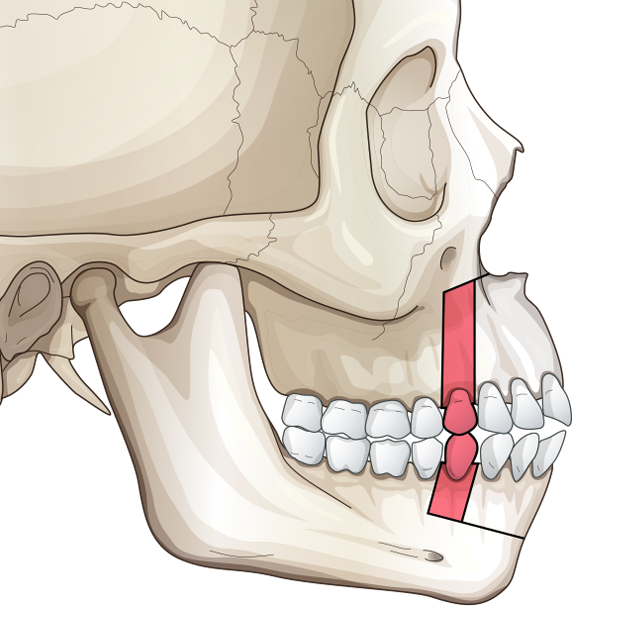

At least 4* of counter clockwise rotation on both jaws.

5mm+ advancement on both maxilla and mandible

7mm+ genioplasty

At least 4* of counter clockwise rotation on both jaws.

5mm+ advancement on both maxilla and mandible

7mm+ genioplasty